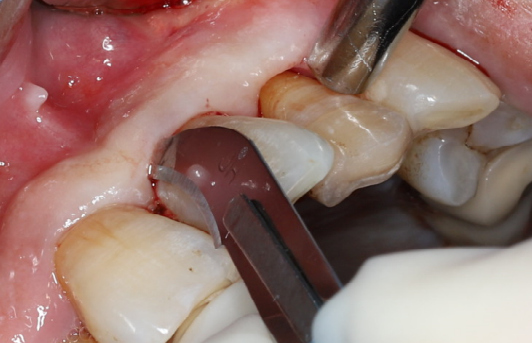

使用12#镰形刀片沿21、22、23做龈沟内切口,于24近中做垂直附加切口。

翻开全厚粘骨膜瓣,暴露22颊侧牙槽骨,微创拔除22。

搔刮22拔牙创,暴露22牙槽骨表面,开放骨髓腔。